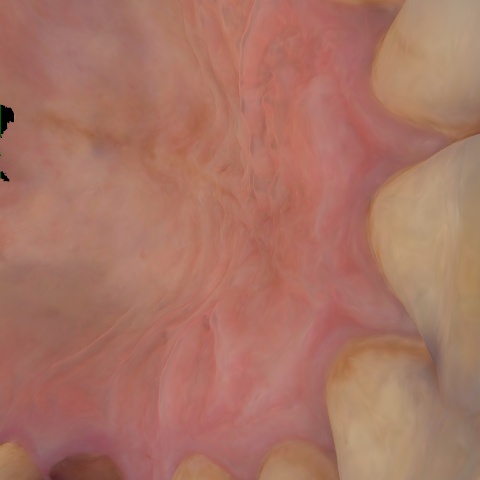

Image 357 / 1743

NHD36692

Annotated as "Good"